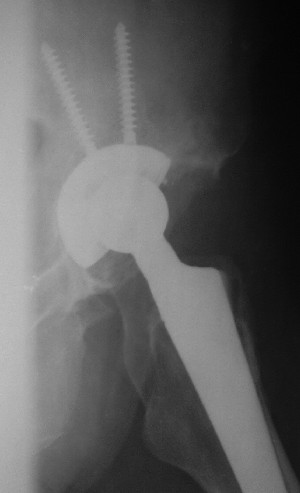

После протезирования прямой 5/04/04

|

Больной 18 мая 2003 года в автоаварии получил перелом левой вертлужной впадины, вывих бедра. Госпитализирован в один из стационаров области.Вывих вправлен. В последствии бедро вывихивалось еще дважды. На консультацию был представлен снимок от 19.05.03г., больной переведен к нам 3.06.03г. Снимок при поступлении - перелом впадины, задне-верхний вывих бедра. 05.06.2003 г. выполнено открытое вправление вывиха левого бедра и остеосинтез стенки вертлужной впадины двумя винтами. Послеоперационный период без осложнений. Объем движений в левом тазобедренном суставе восстановился полностью. Выписан на амбулаторное лечение в удовлетворительном состоянии с рекомендациями 3 месяца ходить на костылях без нагрузки на оперированную конечность. На контрольных рентгенограммах левого тазобедренного сустава 13.10.2003 г. - признаки консолидации перелома; плотность, форма головки и состояние суставных поверхностей удовлетворительные. Разрешена дозированная осевая нагрузка, на конечность с использованием дополнительной опоры. 19.12.2003 г. больной обратился с жалобами на боли в левом тазобедренном суставе. На рентгенограммах левого тазобедренного сустава 19.12.2003 г., 20.02.04г. - асептичекий некроз головки бедра. 5.04.04г. - эндопротез. Сейчас ходит без трости, не хромает. Особенность эндопротезирования - при удалении винтов прослежена линия перелома заднего края впадины и предложено установить чашку несколько меньшего диаметра, чтобы она была покрыта несломанной частью.